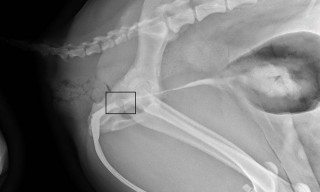

9:30am – Ultrasound of Arthur revealed a generalised thickened bladder wall, but no obvious cause of obstruction. Plain radiography is unremarkable so the team moves on to positive contrast radiography, which reveals a relatively normal bladder neck. However, on repositioning the catheter to get a better view, it’s noted there is a very slight “grating” sensation. Finally, a positive contrast urethrogram reveals the culprit – a single stone wedged around the region of the pelvic brim. Between images the team makes calls to the other, less critical inpatient’s owners and has a cup of tea.